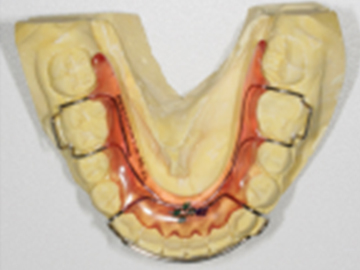

고정식 유지장치를 이용해 교정치료 후 재발을 방지합니다.

가철식 유지장치를 이용해 교정치료 후 재발을 방지합니다.

교정치료 후 일어나는 약간의 재발은 자연스러운 현상 중 하나입니다.

치아와 턱이 생리적으로 가장 편안한 상태를 찾아가면서 일어나기 때문입니다.

하지만, 힘들게 한 교정치료 결과가 다시 예전으로 돌아가는 것은 막아야겠죠!

심다치과에서는 교정치료 후, 위아래 유지장치를 통해 재발이 최소화되고자 합니다.